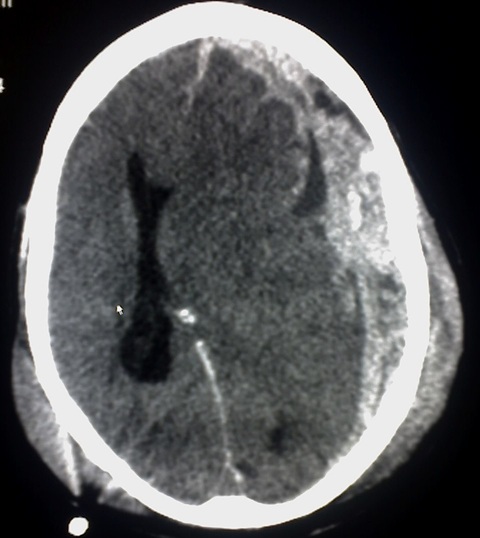

Imagen ilustrativa de hematoma intracerebral

Hematomas intracerebrales

Manejo médico y/o quirúrgico de hematoma subdural, hematoma extradural, hemorragia subaracnoídea traumática, etc, así como el seguimiento posterior.